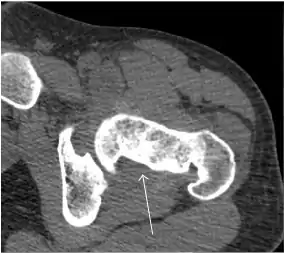

Synovial chondromatosis can be confidently diagnosed by X-ray when calcified cartilaginous chondromas are seen. However, other synovial proliferative processes, such as pigmented villonodular synovitis, require MRI for accurate diagnosis, although noncalcified synovitis can be suspected in radiographs by indirect signs, such as soft tissue swelling and/or erosions in the femoral head, femoral neck, or acetabulum (Figure 7).[1]

Figure 7:

Axial CT image of pigmented villonodular synovitis eroding the posterior cortex of the femoral neck.[1]

X-ray of synovial chondromatosis.[1]

CT of synovial chondromatosis.[1]

In synovial proliferative disorders, MRI demonstrates synovial hypertrophy. In the case of PVNS, characteristic foci of low signal intensity related to hemosiderin deposition are better seen on gradient echo T2* images (Figure 7). In the case of synovial osteochondromatosis, the synovial hypertrophy is accompanied by intermediate signal cartilaginous loose bodies and/or low signal calcified loose bodies.[1]